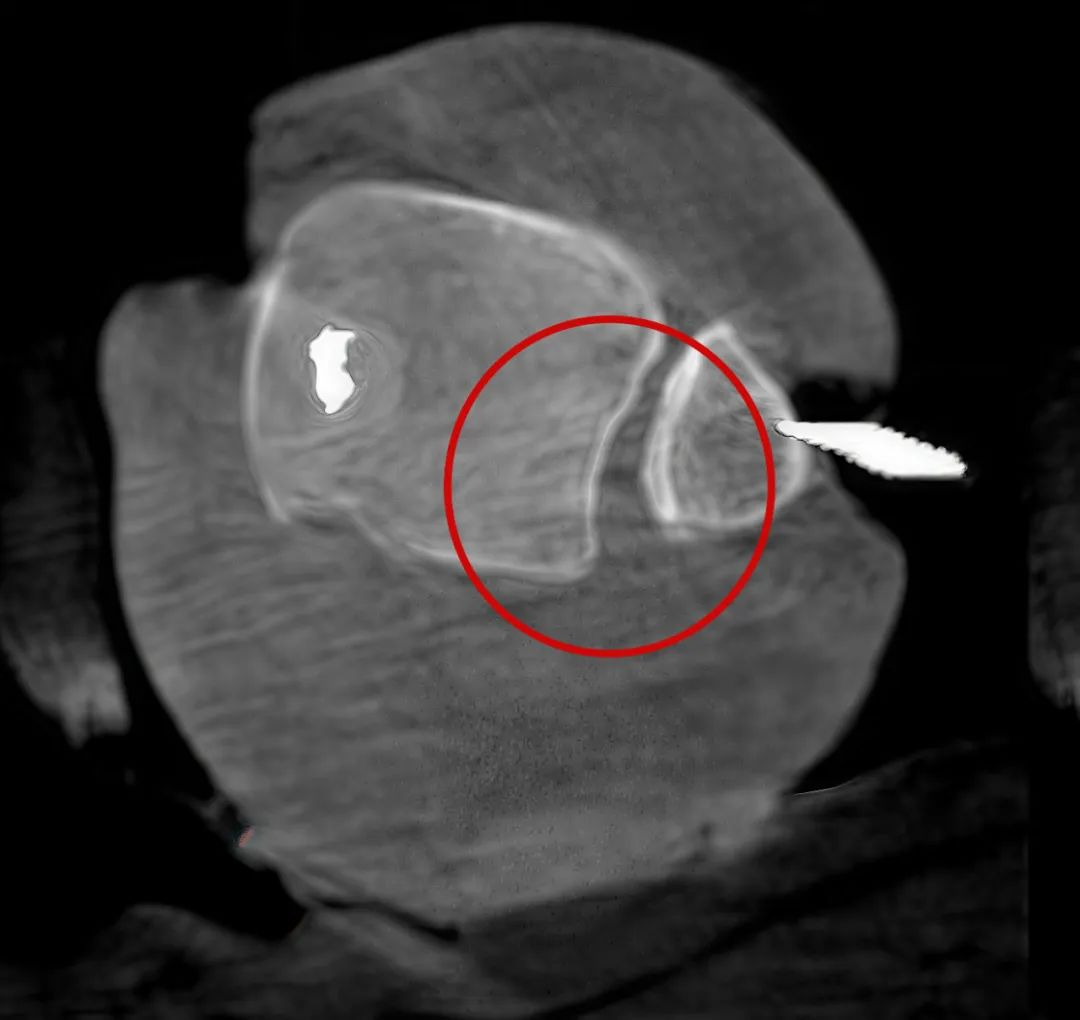

病例1:右側(cè)股骨遠(yuǎn)端骨骺骨病(13歲)

二維影像看不到病灶點

三維切面影像可以看出病灶點